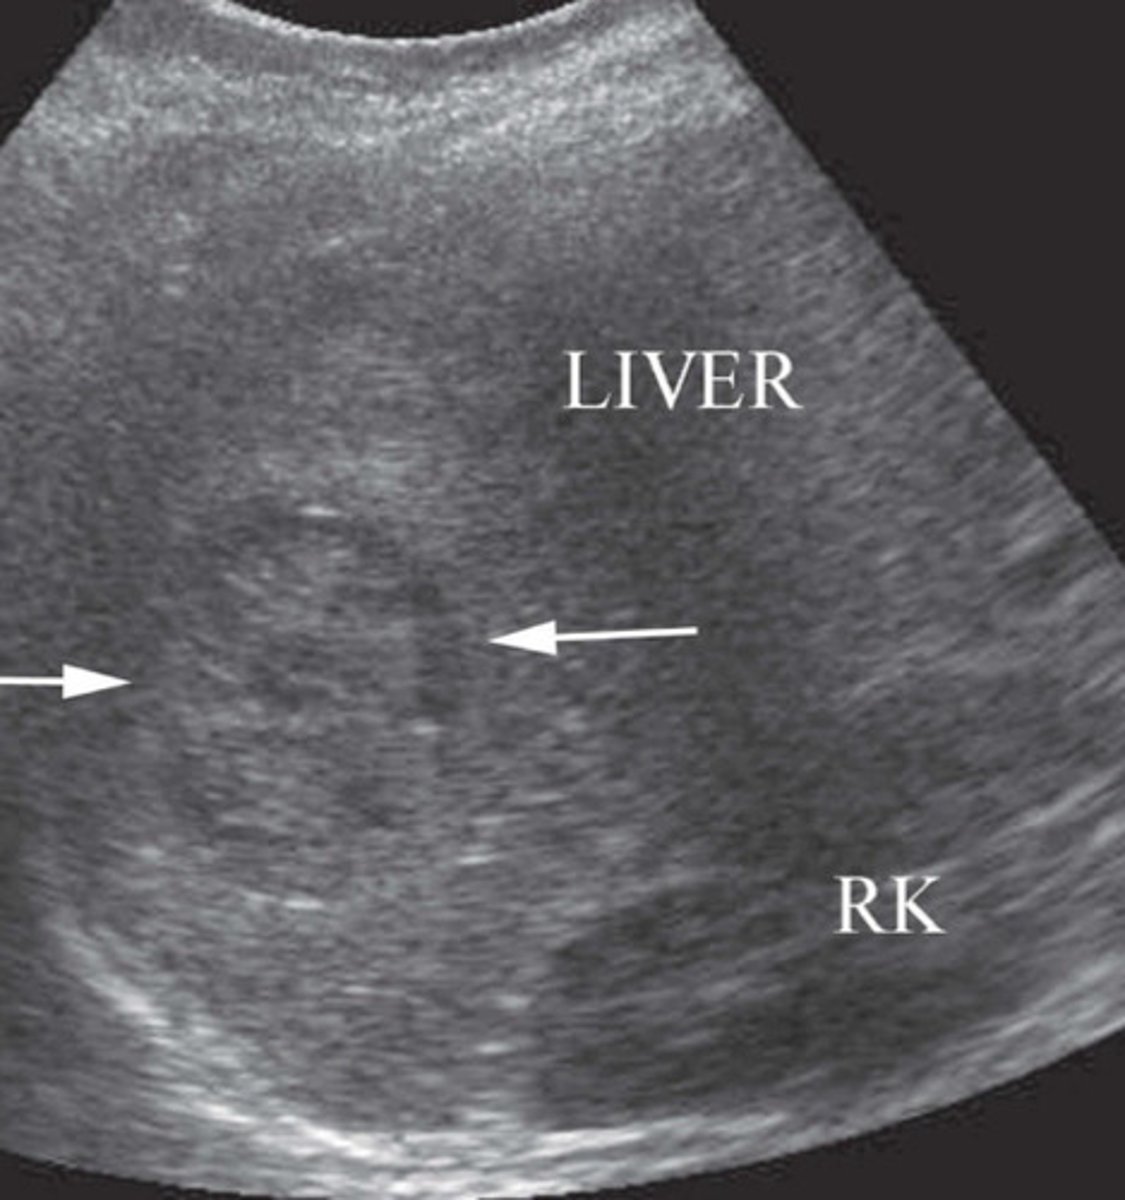

Normal sonographic appearance of liver and kidney

What does this image represent